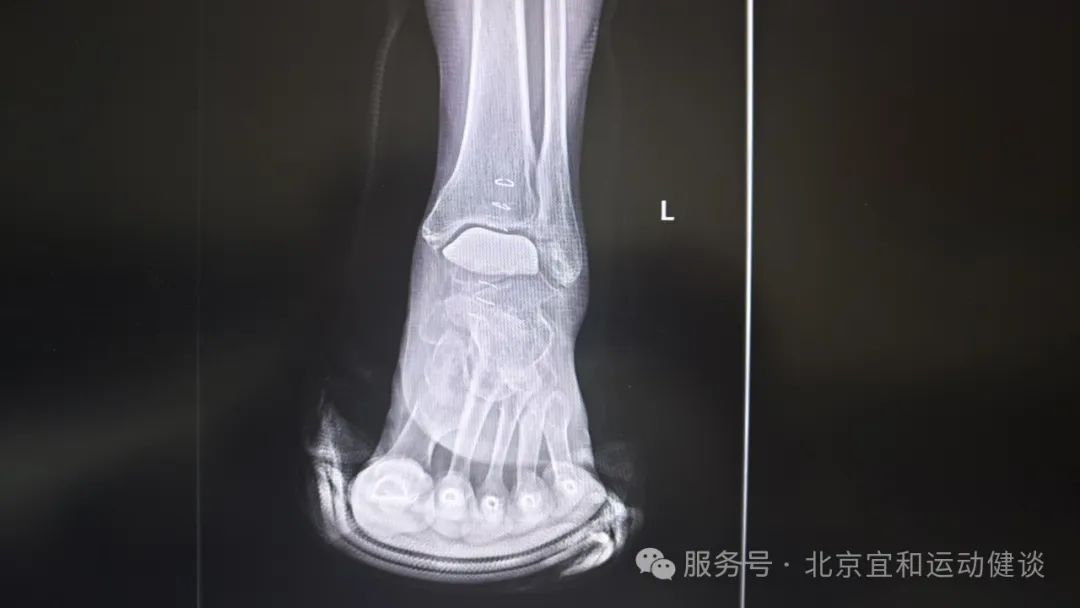

患者術(shù)後(hou)4周複查影像學(xué)資(zi)料